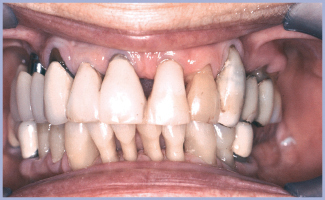

La presenza di atrofia ossea comporta sempre per il clinico una attenta valutazione prospettica sui risultati funzionali ed estetici del caso. È impensabile ottenere risultati estetici in caso di grave atrofia. Il problema dei “triangoli neri interdentali” può essere ridotto, in mancanza di trattamenti più completi e complessi, tramite ricontorno in composito delle corone dentarie. La posizione del labbro a riposo e durante il sorriso è fondamentale nell’evidenziare o mascherare tale inestetismo. Il ricorso a tecniche osteotomiche permette, con intervento scarsamente invasivo, di espandere il sito implantare. L’inserimento dell’impianto immediato in sito post-estrattivo comporta l’applicazione in vario grado di tecniche rigenerative.

Il grado di atrofia condiziona la direzione di inserzione degli impianti. Nel mascellare superiore l’atrofia si verifica nei tre piani dello spazio in senso centripeto e gli impianti saranno inseriti tanto più orizzontali quanto più marcata è l’atrofia. Nel caso in esame si verifica tale evenienza: ne consegue la necessità di usare monconi molto angolati. Monconi di titanio pieni fresabili ci permettono di sopperire alla notevole angolazione tra protesi e impianti. Ovviamente il carico risulta disassato rispetto all’asse implantare: è un compromesso dal punto di vista biomeccanico. Nel caso in esame il carico è ridotto dalla parziale assenza di antagonisti. L’eccessiva angolazione dei monconi comporterà un profilo di emergenza protesico non adeguatamente estetico. Solo una posizione più profonda dell’impianto permetterà di emergere col manufatto con un profilo più edeguato. La presenza di una connessione moncone-impianto in profondità comporta peraltro maggiori rischi di “instabilità microbiologica”. È, infatti, la presenza del gap moncone-impianto responsabile del riassorbimento osseo peri-cervico-implantare. Spesso una migliore estetica sarà un compromesso con il mantenimento microbiologico.

- Fig. 3